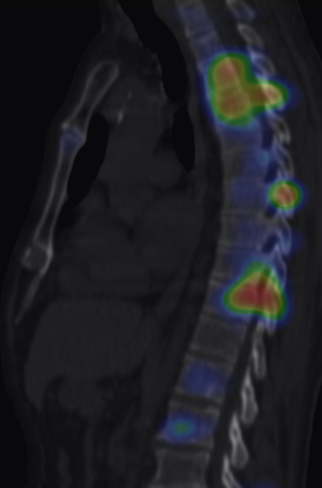

Image

d

5. Multiplex bone metastases. Bone scintigraphy, anterior (a) and posterior (b) whole body scans. SPECT-CT sagittal plane, fusion image (c) and CT image (d). Obvious bone structural changes cannot be identified on the CT scan yet.